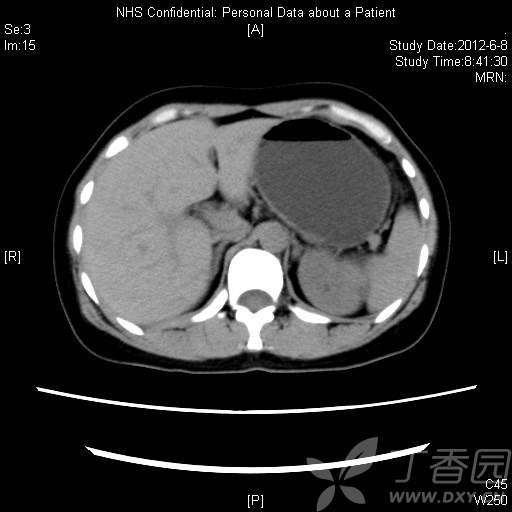

B超:

img